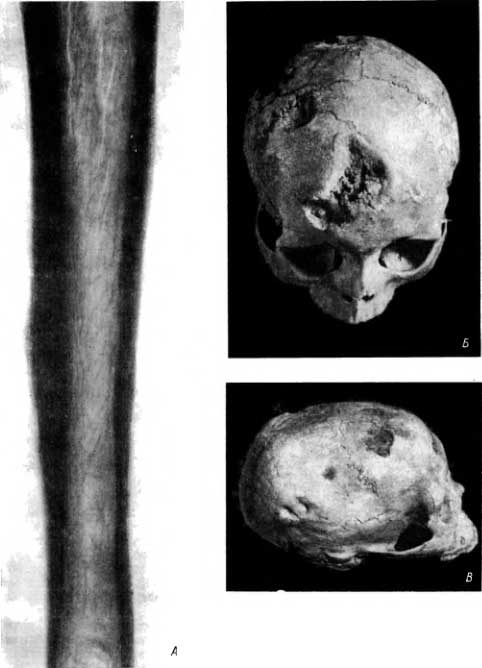

Рис. 101. А — типичный сифилитический остеоперностит на большеберцовой кости; Б — множественные гуммозные деструкции черепного свода, частично сливающиеся между собой; В — множественные гуммозные деструкции черепа.

Начиная с определенной фазы заболевания деструктивные изменения на почве гумм при значительной протяженности поражения сопровождаются, а в дальнейшем в большей или меньшей мере перекрываются эностальным и периостальным костеобразованием (склерозированием). Однако в костях черепа такое преобладание реактивного костеобразования выражено нечасто и выступает значительно слабее, чем в пораженных участках скелета конечностей. Нередко в костях черепа реактивный склероз и костеобразование вовсе не выражены.

На краниологическом материале из старой Вятки хорошо видно, что участки деструкции суживаются в глубине (рис. 101, Б и В). Иногда они имеют более или менее конусовидную форму. Острие «конуса» как бы направлено кнутри.

Эти особенности деструктивных изменений костей черепа на почве сифилиса позволяют отличить их от раковых метастазов, при которых наибольшее разрушение костей обычно наблюдается во внутренней пластинке и в губчатом веществе, а не в наружной пластинке.